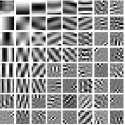

IV-A Transform Learning

To better understand the potential of the MRST model, we vary the number of layers and pre-learn transforms for ST, MRST2, MRST3, MRST5, and MRST7, which possess , , , , and layers, respectively. We used 7 slices of the Mayo Clinic data to train the models. For each model, we run 1000 to 2000 iterations of the learning algorithm to ensure convergence. Fig. 1 shows some of the learned transforms, with each transform matrix row displayed as a square patch for simplicity. The single layer transform displays edge-like and directional structures that sparsify the image. However, with more layers, finer level features are learned to sparsify transform domain residuals in deeper layers. Nonetheless, transforms in deep layers could be more easily contaminated with noise in the training data, since the main image features are successively filtered out over layers.